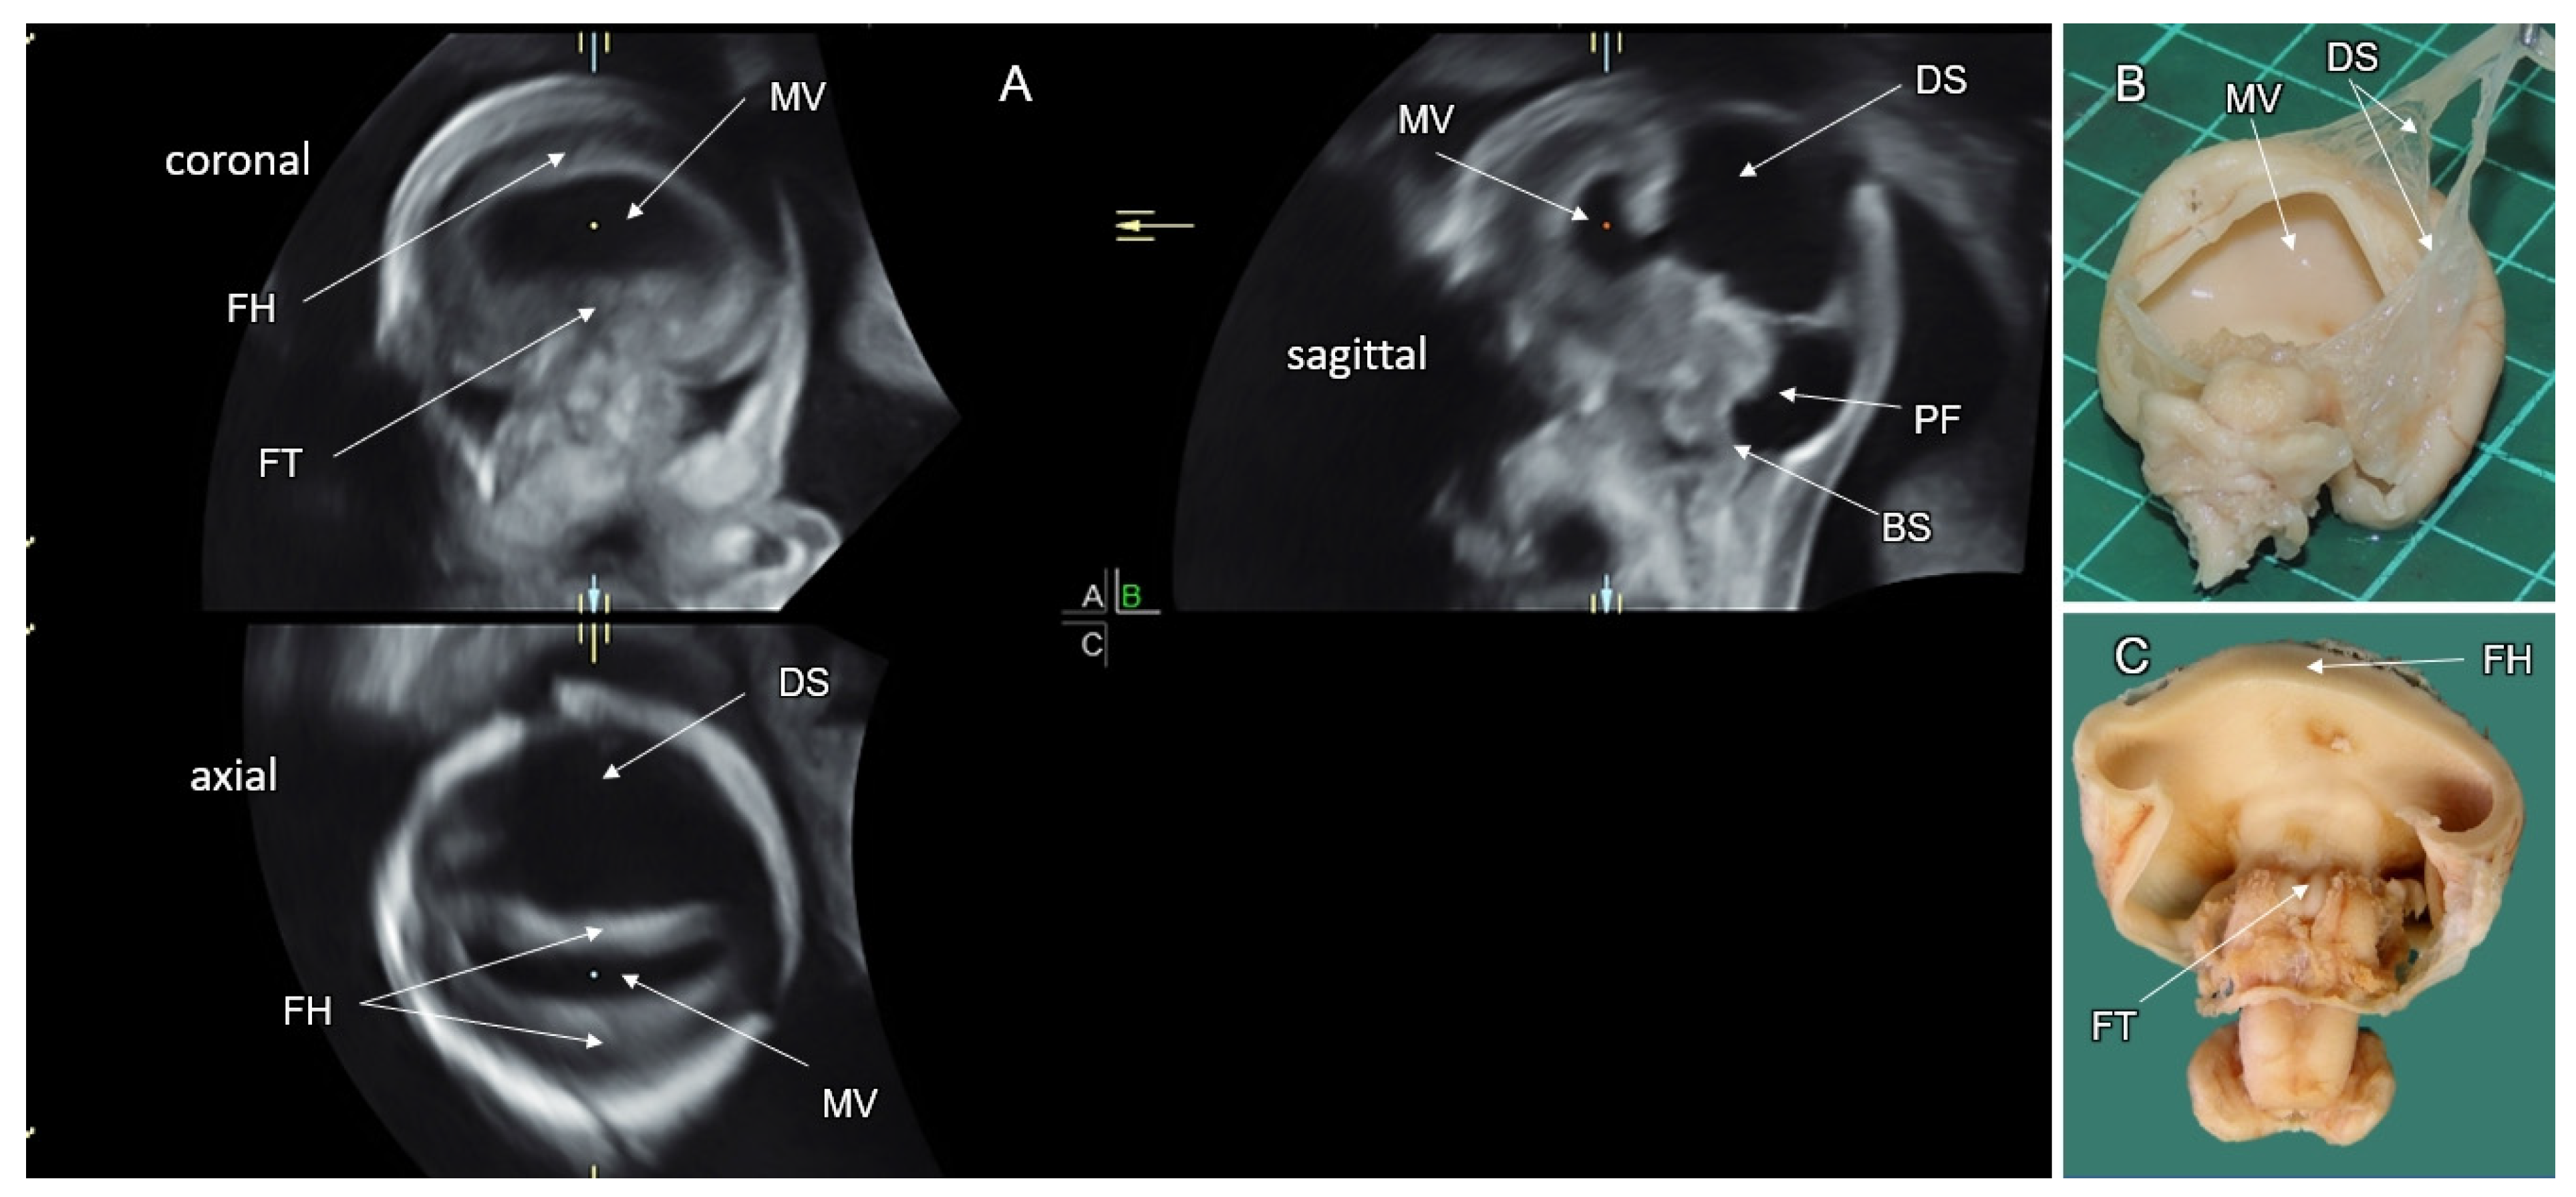

5. Disorders of the Corpus Callosum (DCC)